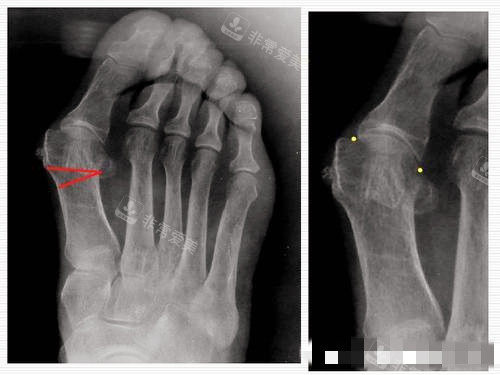

大脚骨X光片

大脚骨外翻程度